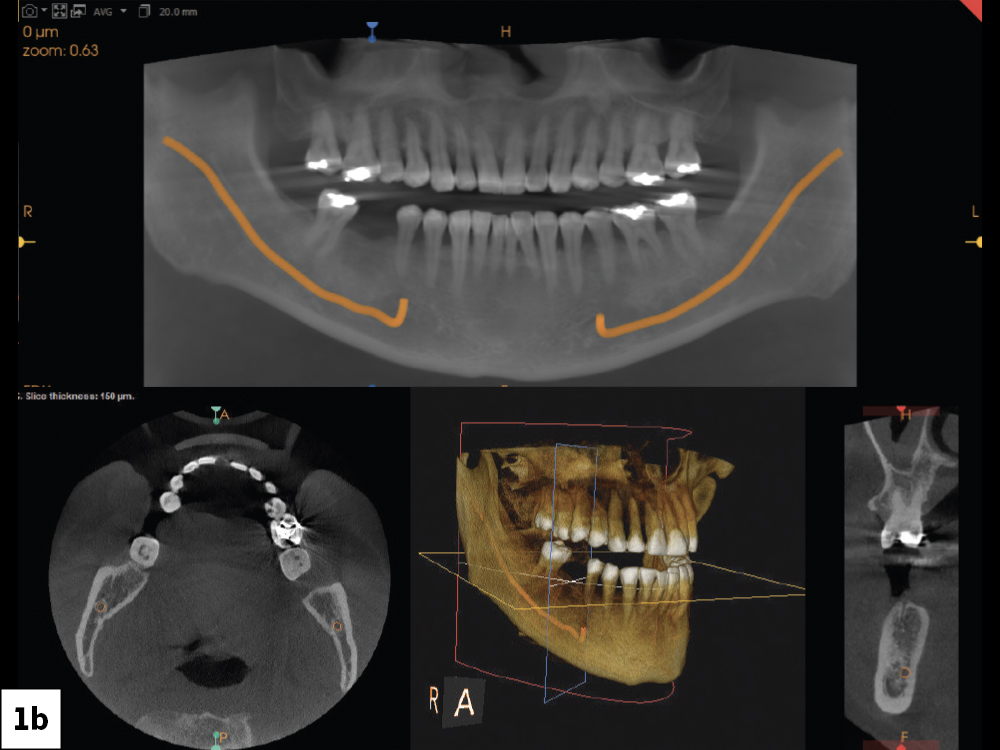

CBCT Scan and Intraoral Measurements to Determine Ridge Dimensions

Figures 1a, 1b: Upon clinical examination, the ridge appeared to have adequate width, though there was some narrowing near tooth #29. A CBCT scan and intraoral measurements allowed me to accurately determine ridge dimensions and evaluate whether there was adequate bone volume for implant placement.